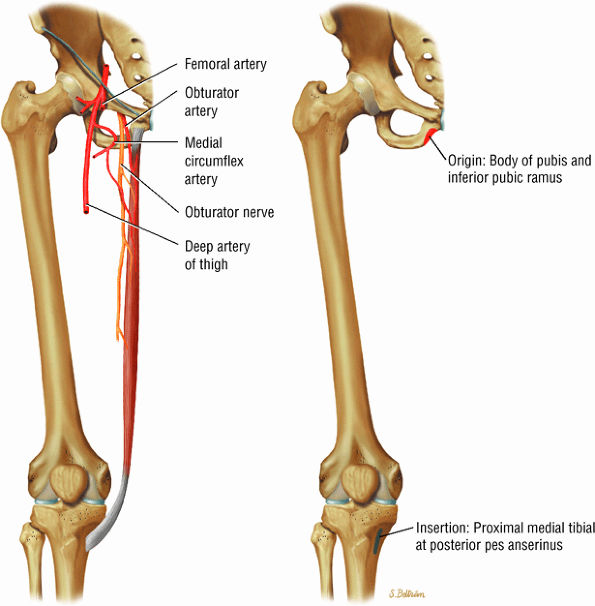

The medial muscles of the thigh, including the gracilis (Fig. 3.10), the pectineus (Fig. 3.11), the adductor longus (Fig. 3.12), the adductor brevis (Fig. 3.13), and the adductor magnus (Fig. 3.14)

FIGURE 3.10 ● GRACILIS The gracilis muscle adducts the thigh and flexes and internally rotates the leg and can be used for anterior cruciate ligament reconstructions. The gracilis is the one muscle of the medial aspect adductors of the thigh that does not attach to the linea aspera of the femur (as opposed to the adductor longus, magnus, and brevis and pectineus muscles).